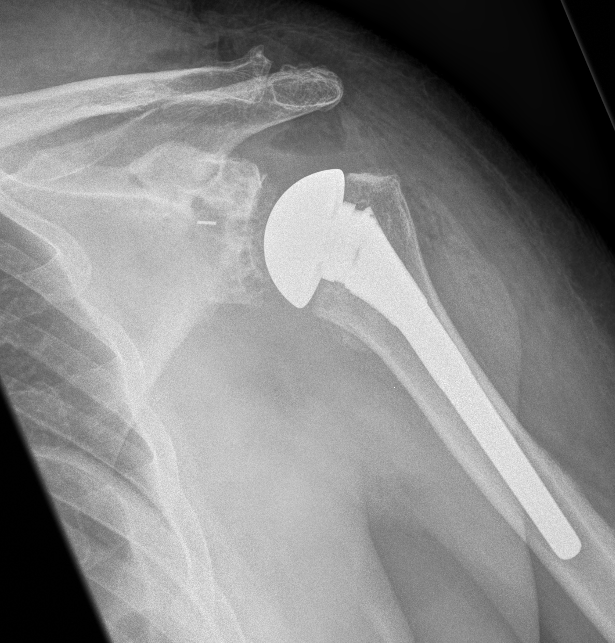

A total shoulder replacement is an open procedure which involves replacing the shoulder joint with a specially designed prosthesis. The prosthesis consists of two components. The first is a humeral head component, which is a metal ball that is secured into the humeral bone with a stem. The other is a glenoid component, which replaces the glenoid and allows smooth movement of the new humeral head. The system provides a close replication to the shoulder joint and relieves pain and discomfort by replacing the severely affected joint. The wound is generally closed with absorbable sutures. However, instructions will be given by Dr Cutbush post-surgery as to wound and dressing procedures.

Following surgery an xray and usually a CT scan will be performed day one postop to check that the position of the prosthesis is satisfactory. Physiotherapy will be commenced day 1 postop and patients will be given a rehab programme by their physiotherapist.